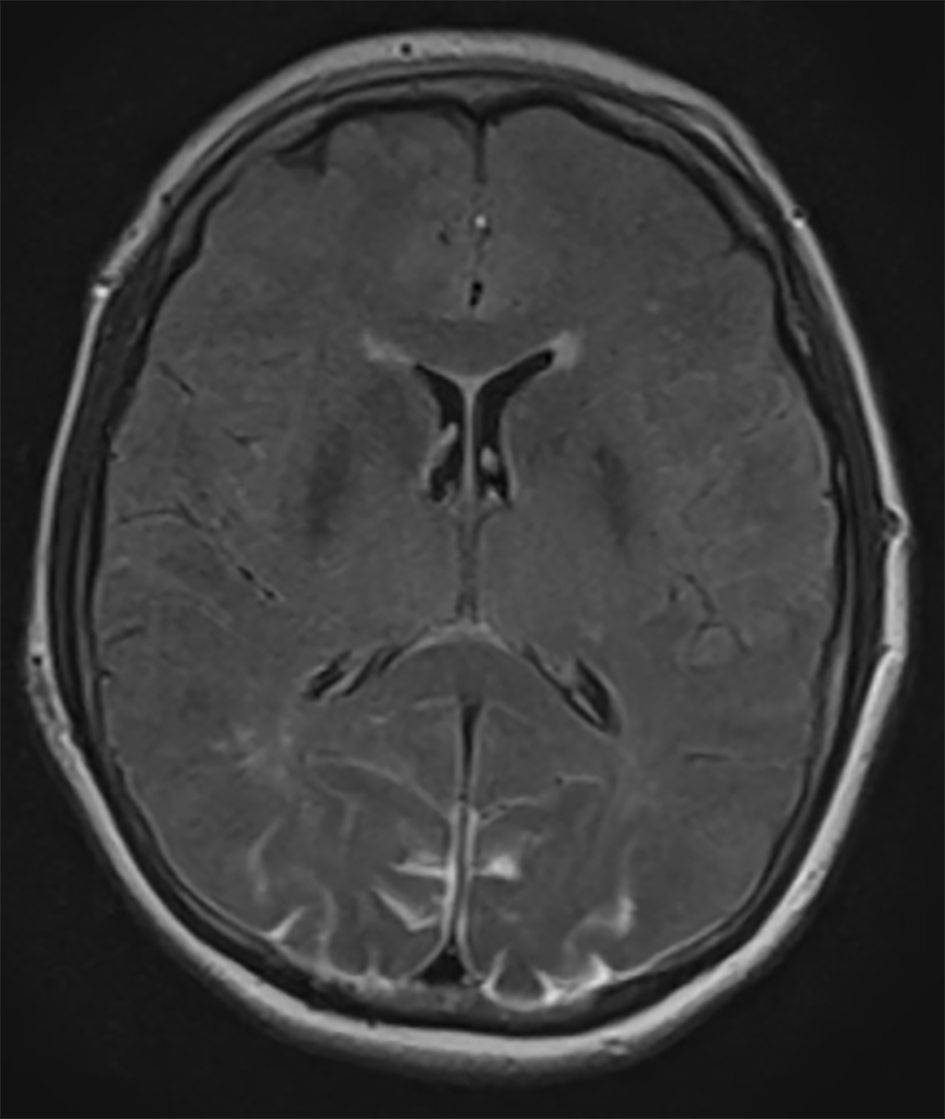

An urgent MRI of the orbits and brain was performed. There were no pathological findings in the orbits. Brain MRI showed occipital lesions with T2 hyperintensity and pathological signal in FLAIR sequence in subcortical regions of both occipital lobes, suggestive of PRES (Fig. 1). A postoperative stroke study showed no signs of decreased perfusion.

![]() Click for large image | Figure 1. Axial FLAIR MRI demonstrating bilateral occipital lobe hyperintensity, suggestive of blood or edema. Because the images from other brain MRI sequences were normal, the patient was diagnosed with PRES. |